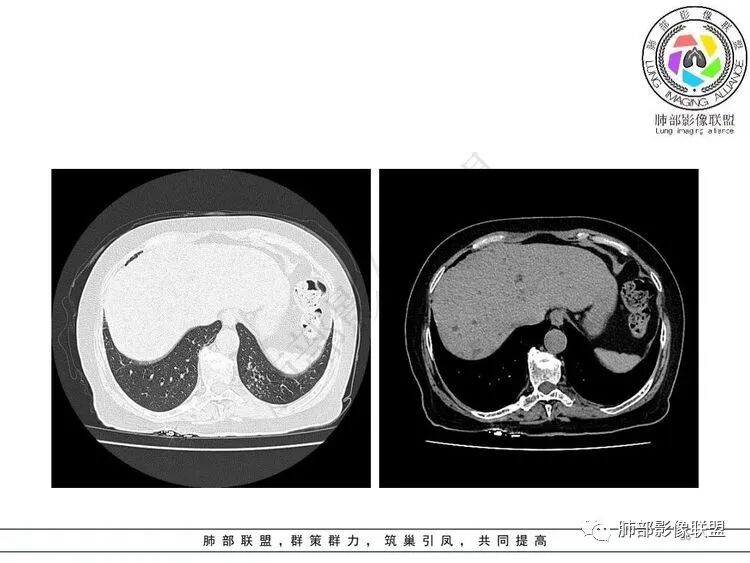

左肺上叶大片状实变,边缘部分清晰,密度不均,支气管部分扩张扭曲,同时散在分布小透光区,左下肺沿肺段及纹理走形斑点,粟粒影及树芽征。考虑左肺感染性病变,结核首选,其它感染待排

女,65胸闷,气促半月入院,左肺上叶见大片状实变影,边缘模糊,其内见含气支气管征,支气管管壁不规整,凹凸不平,广泛性狭窄、僵硬、扭曲,左肺下叶另见粟粒,结节及树芽征征,结核感染T细胞阳性,考虑结核可能,除外其它感染性病变。

3.左肺上叶较大范围实性密度区,密度偏高不均,支气管穿行且轻度扩张,可见无壁不规则空洞(未能显示外壁),未显示液平或腔内结节。

4.左肺下叶多发结节影及条索影,密度不均,边界较清楚,可见树芽征。

1.左肺上叶较大范围实性密度区,支气管未见阻塞,无壁空洞,整体比较“干”,加之纵隔左移,比较符合病程较长的结核性病变。

左肺下叶多发结节影、条索影、树芽征等具有相当明显的提示意义—符合继发性肺结核。